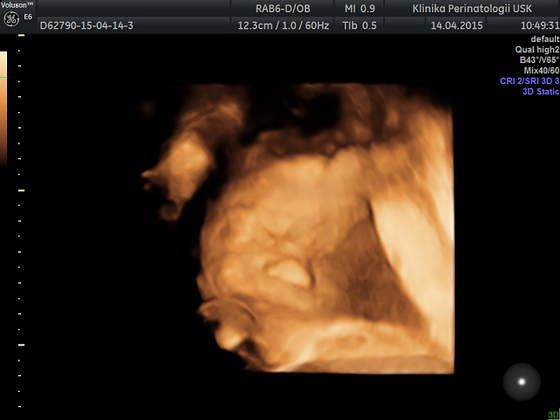

Ja też dziś miałam usg ale to młodzi doktorzy robili, więc bez szczegółów... mieli problem ze złapaniem czegokolwiek ale kawałek twarzyczki widać, szkoda tylko że nóżek nie chciał rozłożyć żeby pisiorka pokazać

a to Tymonek 24t 4d

O jaki dziubek slodki sobie śpi:-*